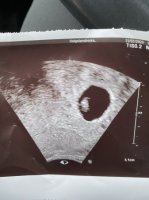

Tenkte vi kunne ha en tråd hvor vi legger ut TUL bildene våre. Det er så fantastisk å se på synes jeg  og nå begynner jo folk å få timer til TUL også, og noen har allerede verdt. Så da kjører vi på med en tråd tenker jeg

innvendig hos meg iallfallInnvendig ul dere har?

Innvendig herInnvendig ul dere har?

Tok de innvendig eller utvendig? Skal på TUL i dag, 9+1Lille nurk8+5 ca

21mm på 8+5? Sikker på at du ikke er litt lenger på vei? Jeg er 20mm nøyaktig idag, og jeg er 9+0Innvendig, 8+5lille var 21mm

mente den hadde hjerterytme på over 150. Hun trodde også jeg var kommet litt længer på vei(skulle egentlig vært 7+0)